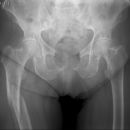

Femurschaftfraktur